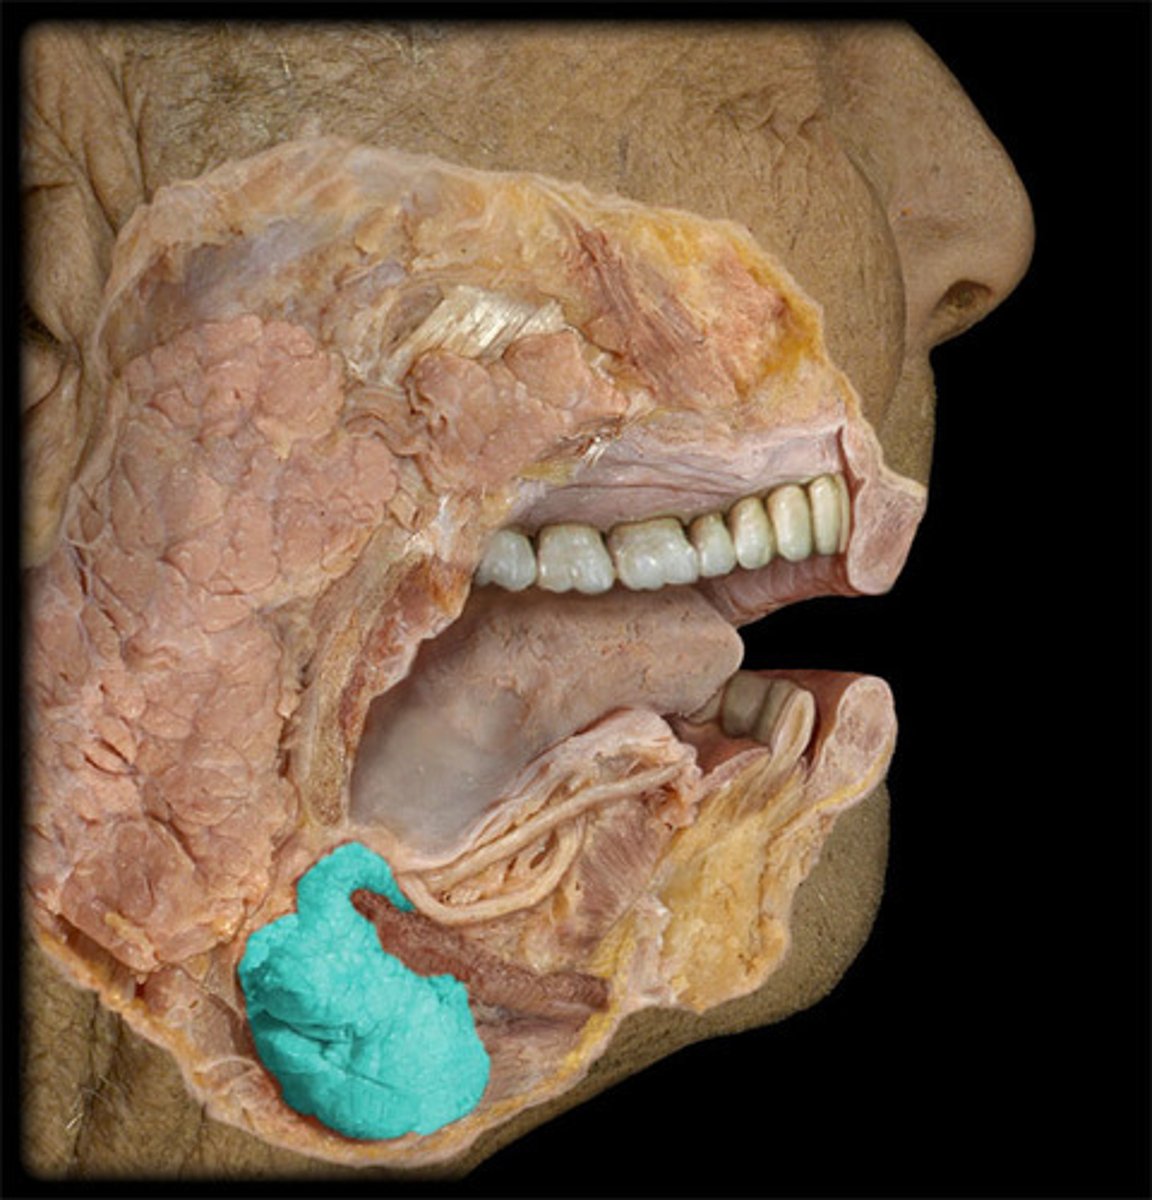

Parotid Salivary Gland

Submandibular Salivary Gland